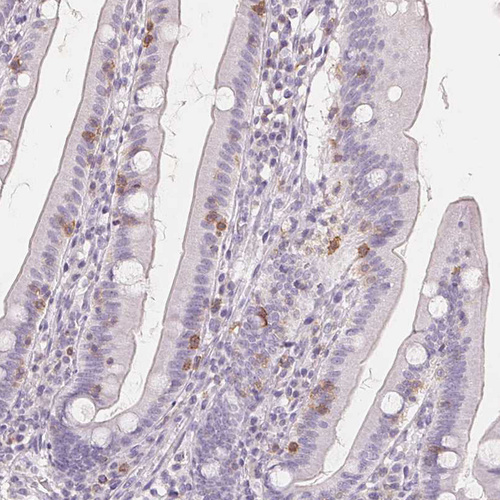

Immunohistochemistry analysis in human lymph node and skeletal muscle tissues using HPA050525 antibody. Corresponding CD69 RNA-seq data are presented for the same tissues.